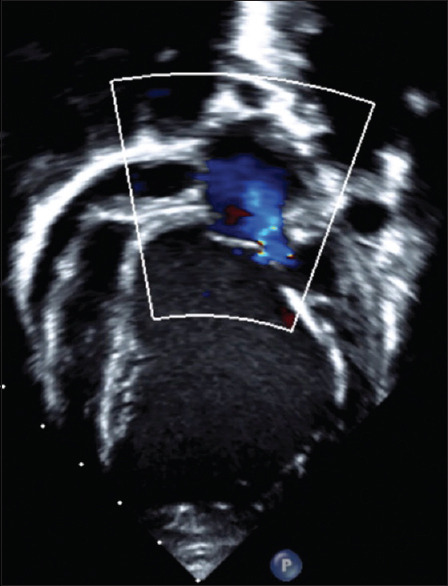

Anomalous left coronary artery from the pulmonary artery (ALCAPA) is a rare congenital heart disease, presenting either in isolation or with other cardiac anomalies. The most common presentation is congestive heart failure in infancy, though some may remain asymptomatic till adulthood. A 5-month-old infant with congestive heart failure was diagnosed to have ALCAPA with severe Left ventricular (LV) dysfunction. Unlike the more common variants where the left coronary artery (LCA) arose from the facing sinuses, the LCA arose from the left anterior nonfacing sinus of the pulmonary artery at a considerable distance from the left aortic sinus. This made direct reimplantation of LCA to the aorta challenging. LCA was reimplanted to the aorta using an extrapulmonary baffle made of an autologous pulmonary flap. The postoperative period was uneventful. The LV contractility improved during the follow-up. Early diagnosis and intervention with a novel surgical technique prevented irreversible cardiac complications and mortality.